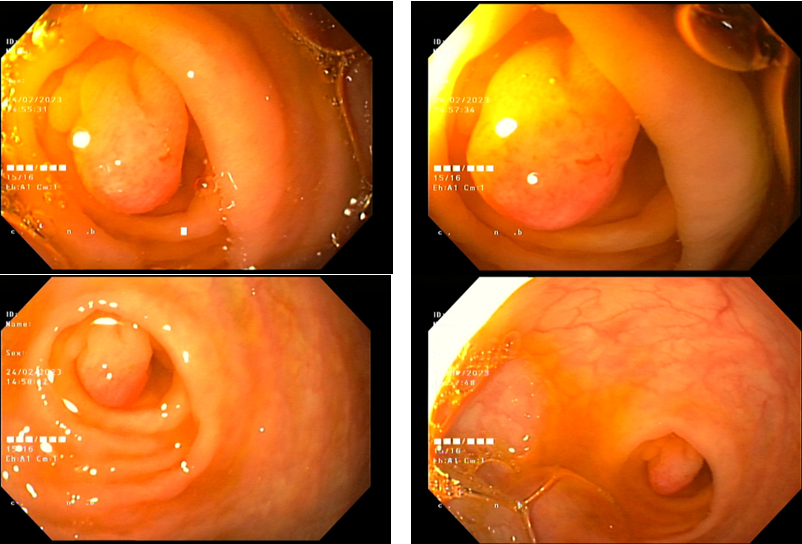

Polyp tại lỗ ruột thừa - một trường hợp hiếm gặp

11/17/2023 8:50:00 AM

Vừa qua, khoa Tiêu hóa Bệnh viện trẻ em Hải Phòng đã nội soi đại tràng, cắt gọn polyp kích thước 0,5 cm tại lỗ gốc ruột thừa, tránh cho bệnh nhân 14 tuổi ca phẫu thuật không cần thiết